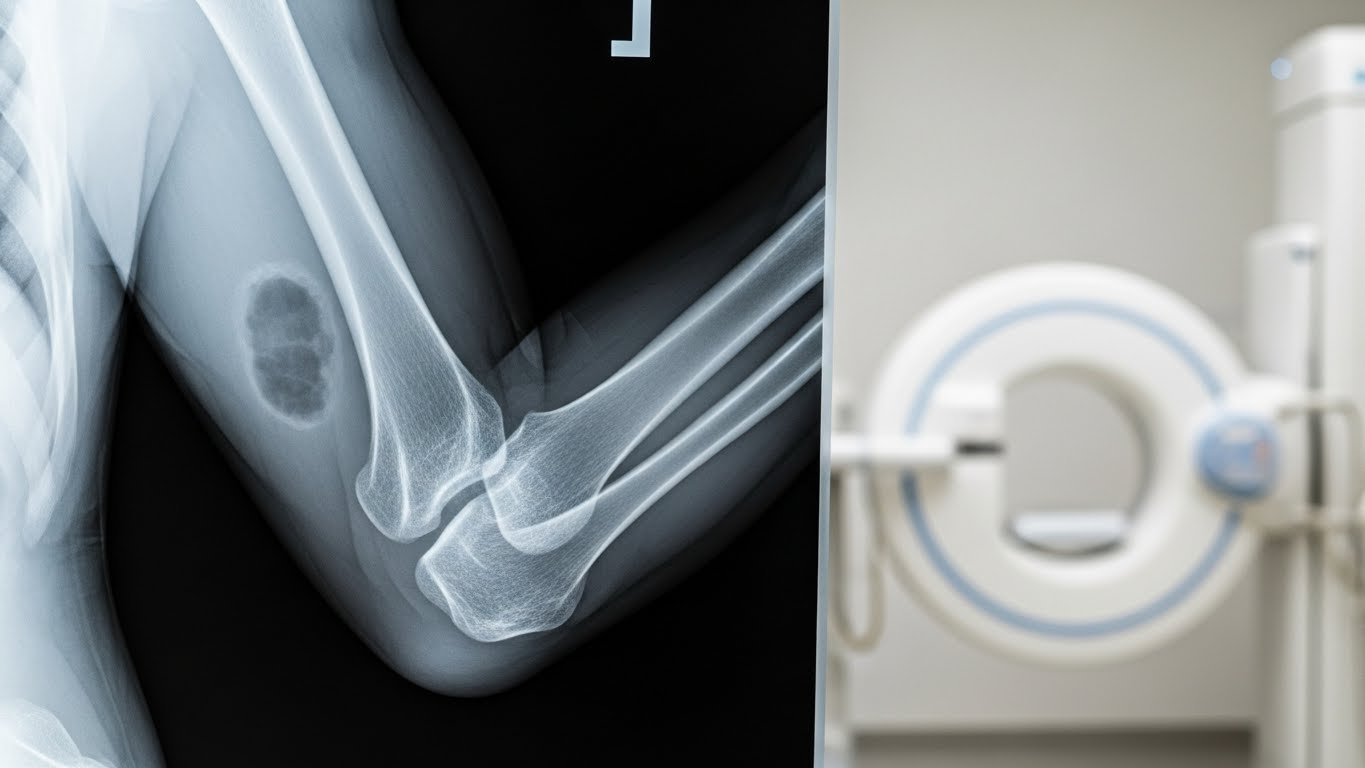

Qu’est-ce qu’une radiographie du coude ?

La radiographie du coude est un examen d’imagerie médicale qui utilise les rayons X pour visualiser les structures osseuses de votre articulation. Selon les recommandations de la Haute Autorité de Santé (HAS), cet examen reste l’examen de première intention pour évaluer les traumatismes du coude.

L’examen permet de visualiser trois os principaux :

- L’humérus (os du bras)

- Le radius (os de l’avant-bras, côté pouce)

- Le cubitus ou ulna (os de l’avant-bras, côté auriculaire)

Contrairement à l’IRM ou au scanner, la radiographie standard se concentre exclusivement sur les structures osseuses. C’est un examen rapide, indolore et sans préparation particulière.

Les différentes vues radiographiques du coude

Pour obtenir une analyse complète de votre coude, le manipulateur en radiologie réalise généralement plusieurs clichés sous différents angles :